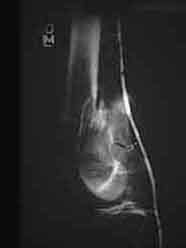

An initial injury film shows a closed supracondylar femur fracture with an arteriogram done for questionable signs of arterial injury showing a nonocclusive intimal flap of the popliteal artery. Since this arterial injury fit the published criteria for nonop observation, our orthopedic surgeons went ahead and did ORIF. 6 weeks later a F/U angio shows complete resolution of the intimal flap -- unnecessary surgery thus avoided.

6 weeks later

I'll try--there is an intraluminal defect consistent with a flap.

Click to zoom in on these images:

with regard to this image i imagine i see what eric is talking about but still think that this could be spasm. Eric any other views?